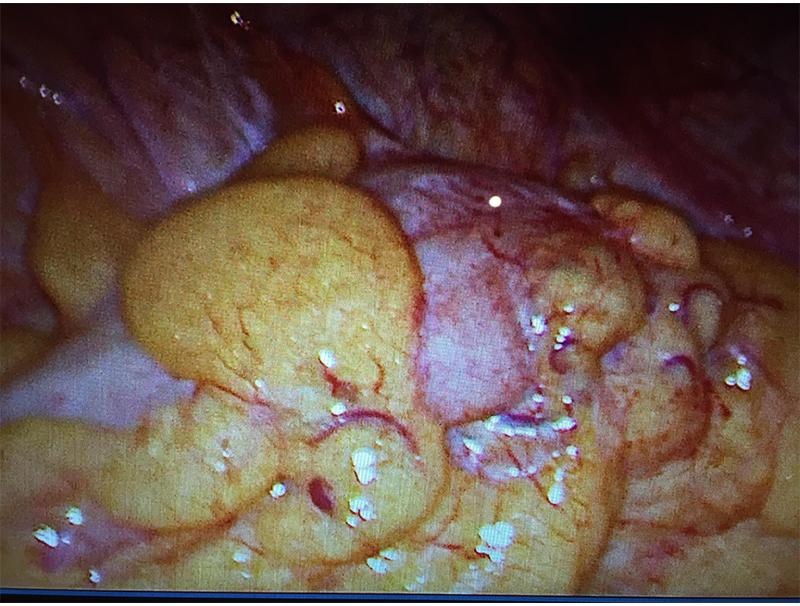

60 year old lady with an episode of sigmoid diverticular perforation with was managed with antibiotics and other supportive measures. A surgery was avoided at this time. She settled well, however started experiencing recurrent incapacitating abdominal pain due to sigmoid diverticular disease. A laparoscopic sigmoid colectomy and colorectal anastomosis was electively performed. She was discharged on postoperative day 5. She is now completely pain and symptom free.

Patients who have been managed by conservative treatment in the initial attack may continue to suffer due to frequent minor attacks of acute inflammation or get recurrent abdominal pain due to chronic inflammation, adhesions, kinks, fibrosis or a stricture formation. This may require an elective surgery as was performed in above case. This surgery is safely performed laparoscopically reducing stay and discomfort and enhancing patient recovery.